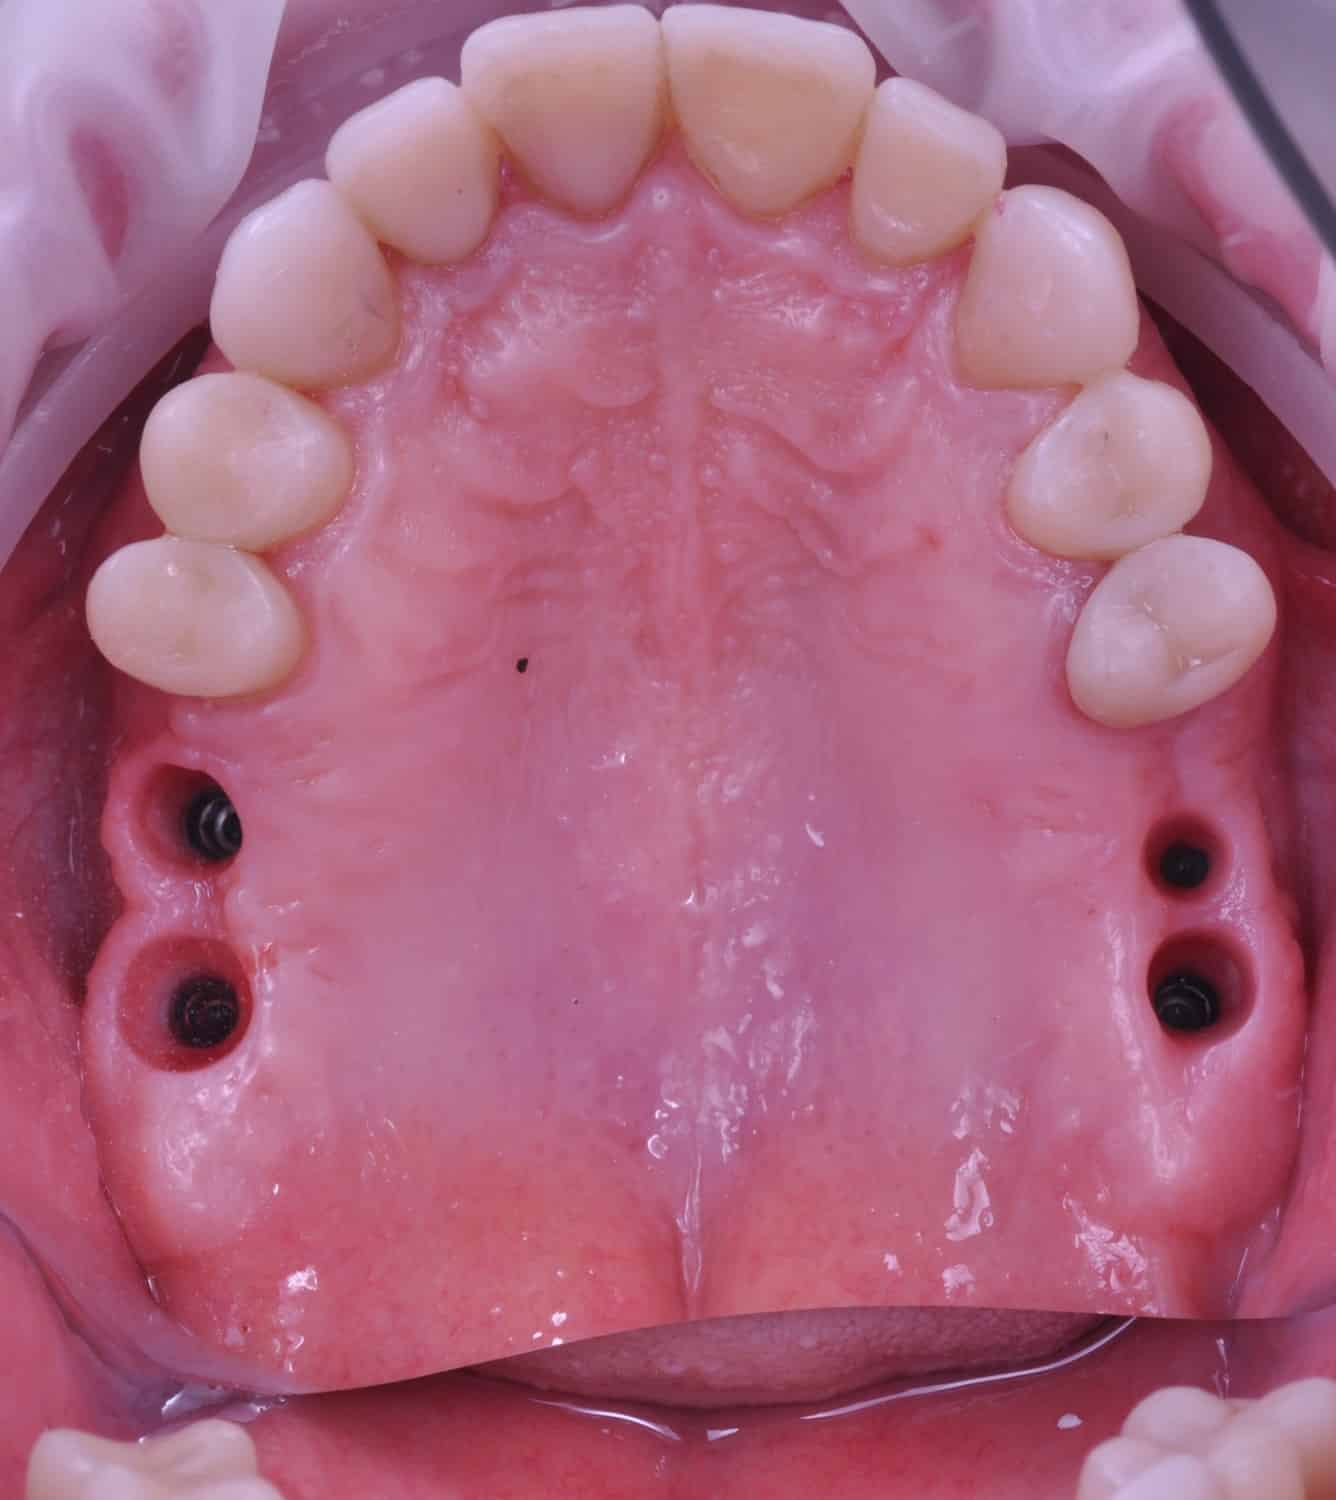

Împreună cu pacientul, am optat pentru inserarea implantelor cu ajutorul ghidului chirurgical pentru a plasa implantul în poziția protetică ideală și pentru a permite realizarea coroanelor insurubate pe implant. A fost efectuată scanarea digitală a arcadelor și a ocluziei pacientului, iar împreună cu tehnicianul radiolog de la DigiRay a fost suprapus fișierul .stl al amprentei digitale peste fișierul .dcm de la CBCT, utilizând software-ul 3Shape.

S-a planificat individual poziția și axul de inserție al fiecărui implant.

Avantajele realizării intervenției cu ajutorul ghidului chirurgical au fost:

Doar astfel putem crea profilul de emergență corect al coroanei dentare, ceea ce permite conformarea papilei și a sulcusului.